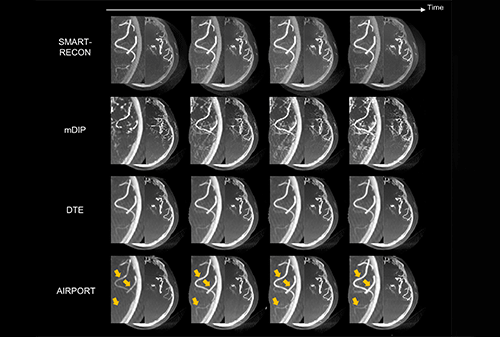

2025-01-21IEEE TMI | High Time Resolution CT ImagingRecently, researchers Li Yinsheng and Liang Dong from the Medical Artificial Intelligence Research Center of Shenzhen Institute of Advanced Technology, Chinese Academy of Sciences, and the Key Laboratory of Medical Imaging Science and Techn...

View More